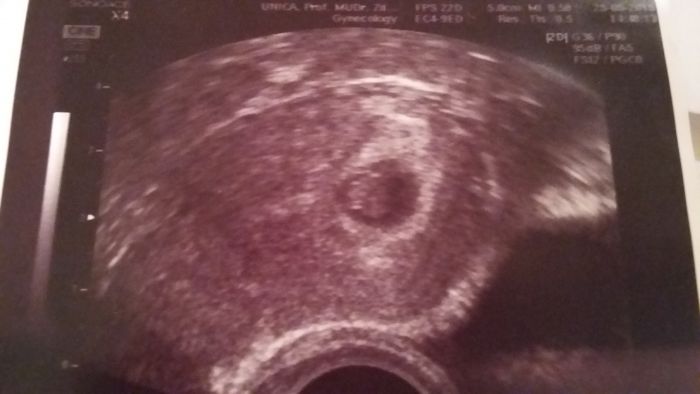

Ahojky holky, tak jsem dnes byla na kontrole u svého doktora a mám super zprávy! :) Jak všichni vite měla jsem jít včera na revizi,protoze v pátek jsem krvacela,v nemocnici odhadli gest.vek o 3 týdny Starší a ze neprospiva protože není srdíčko. Samozřejmě jsem nikam nešla. Dle PM jsem dnes 5+4, dle ultrazvuku 6+6 ale teď to hlavní. Jeho maminka dnes poprvé viděla a i slyšela jeho srdíčko!! Když jsem jela tramvaji domu museli si o mě myslet, že jsem blázen protože jsem se usmivala a tekly mi slzy jak hrachy :) Takže vám řeknu jedno: kdybych neměla prisnej klidovej režim půjdu té doktorce do nemocnice rozbit hubu! :-D Prikladam foto melo broucka :)